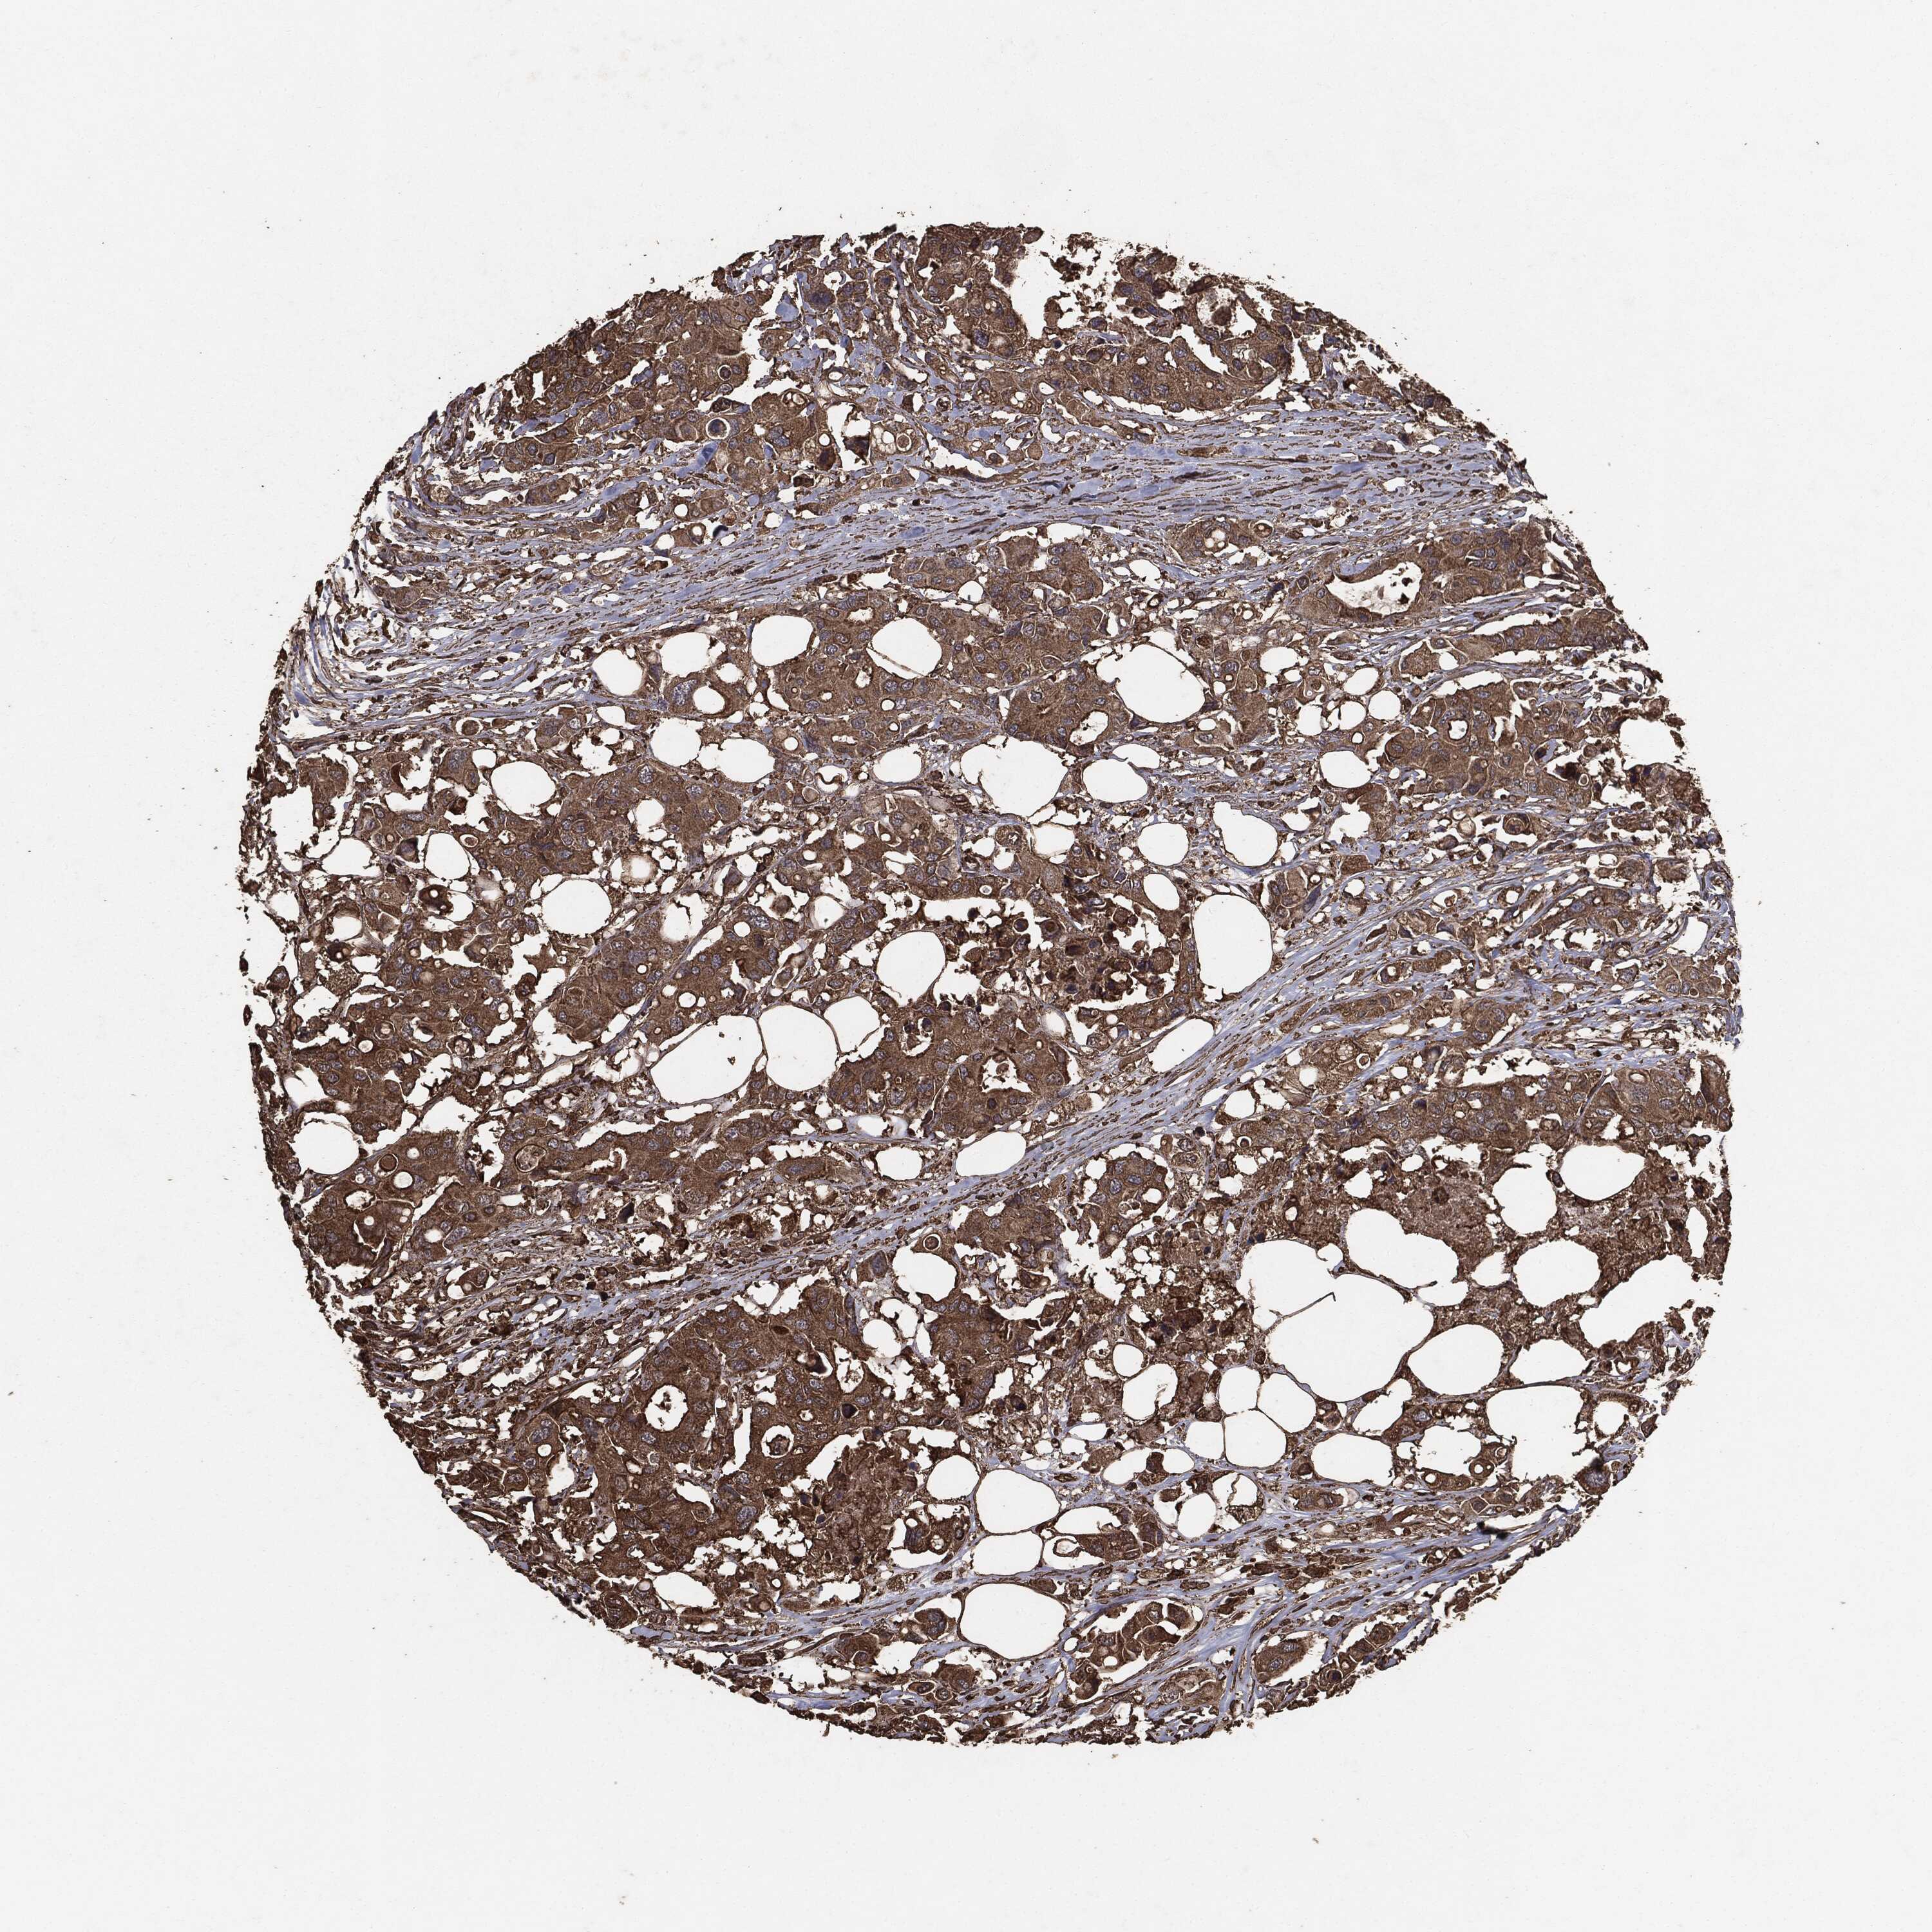

CANCER COLORECTAL CANCER Show tissue menu

Colorectal cancer

Human cancer

Colon adenocarcinoma